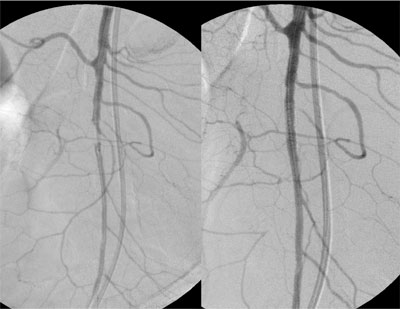

Paciente de 84 anos, sexo feminino, hipertensa, portadora de fibrilação atrial crônica e marcapasso definitivo associado a insuficiência coronariana. Procurou atendimento por apresentar forte dor abdominal em cólica, iniciada há poucas horas e que não cessou com uso de analgésicos tradicionais. Ao exame físico, observou-se ritmo cardíaco irregular por fibrilação atrial crônica e dor abdominal difusa à palpação profunda, sem sinais de descompressão dolorosa do abdome. Indicado estudo angiográfico realizado cerca de 3 horas do inicio da dor, que demonstrou oclusão do terço médio da artéria mesentérica superior. Realizado tratamento endovascular, mediante trombólise mecânica associada ao implante de stent em estenose localizada no terço médio da artéria mesentérica superior, sem intercorrências. Paciente permaneceu internada em Unidade de Terapia Intensiva, encontrando-se hemodinamicamente estável no primeiro dia após o procedimento. Entretanto, como os padrões laboratoriais de acidose metabólica e leucocitose com desvio à esquerda permanecessem, foi submetida à laparotomia exploradora sendo encontrado segmento cianótico, sendo optado preventivamente por ressecção de 70 cm de intestino delgado à 2m do ângulo de Treitz sem intercorrências. Após melhora dos padrões clínicos e laboratoriais, recebeu alta da UTI, permanecendo internada no mesmo Hospital. No 10 dia pós operatório a paciente apresentava desconforto abdominal, sendo realizado nova arteriografia que mostrava a perviedade da artéria mesentérica superior. No trigésimo dia pós operatório a paciente se alimentava e apresentava evacuações normalmente mas mantinha desconforto abdominal e leucocitose. Foi submetida a uma nova laparotomia sem achados de isquemia ou de infecção na cavidade.